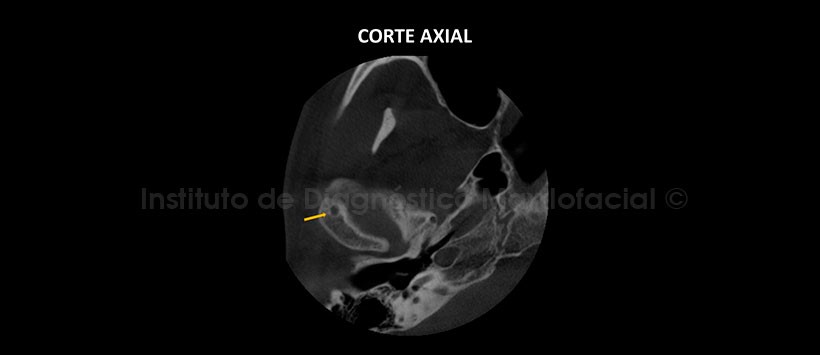

A la evaluación de la tomografía volumétrica (CBCT) de la ATM en boca cerrada, en cortes axiales (Figura 2), coronales (Figura 3) y sagitales (Figura 4), se aprecia aplanamiento y erosión de la vertiente anterosuperior del cóndilo mandibular del lado derecho con presencia de osteofito e imagen hipodensa localizado próximo al polo externo compatible con quiste subcondral (quiste de Ely), además se aprecia disminución de los espacios articulares a nivel posterior. En la tomografía de ATM en boca abierta se evidencia una disminución en el desplazamiento y trayectoria condílea en ambos lados compatible con Hipomovilidad articular.